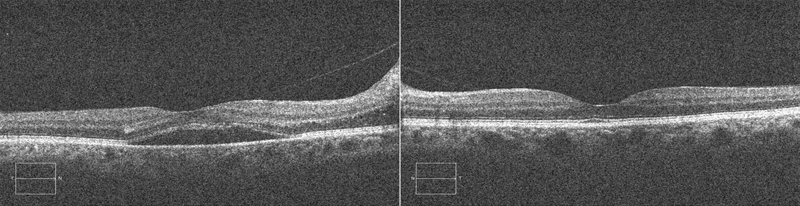

La AV a los dos meses es de 0,5 en OD y 0,8 en OI. La funduscopia revela palidez papilar y envainamiento vascular peripapilar en OD, y en el OI, un edema de papila en fase de resolución (

Figura 4. Retinografía: se aprecia aspecto papilar bilateral tras finalizar el tratamiento.

Palidez papilar y envainamiento vascular peripapilar en OD. Edema de papila en fase de resolución en el OI.